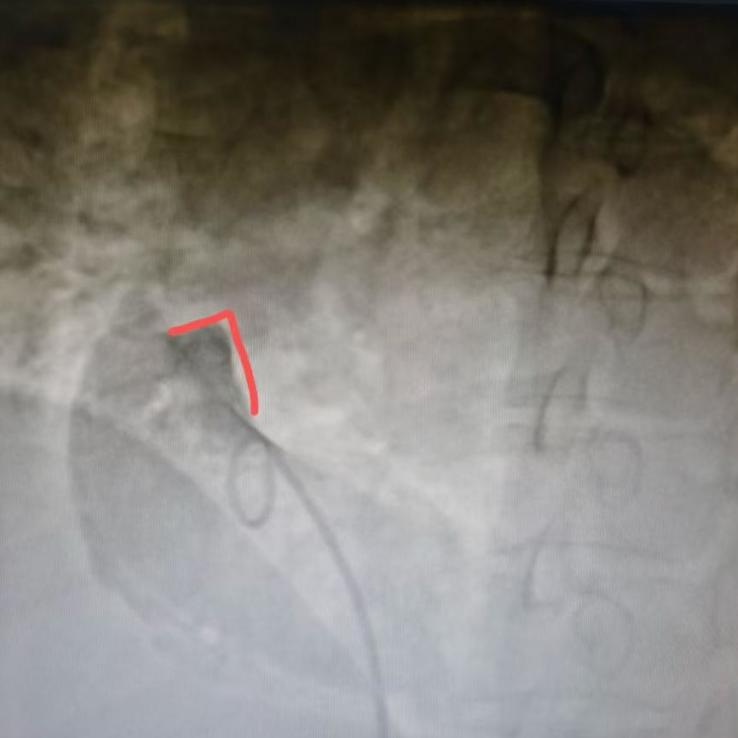

术中,经股静脉猪尾导管行右心耳造影,发现患者右心耳存位置偏低且偏外侧,形态相对狭小。唐艺加医生依据该解剖特点调整操作策略,将新型心房主动固定无导线起搏器精准输送至右心耳基底部,利用其特有的双螺旋设计,将起搏器被牢固地锚定在右心耳,整个手术过程顺利用时仅40分钟。术中定位一次并释放成功。

左前斜:递送鞘造影定位植入位点